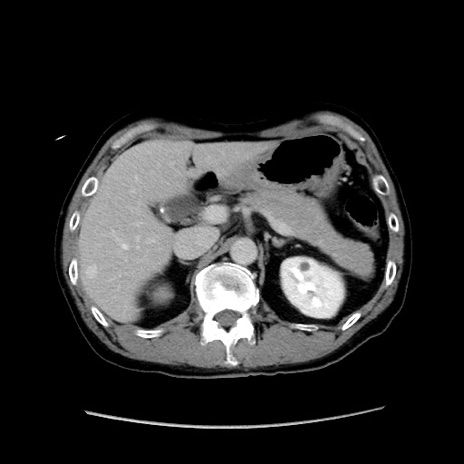

冠状断像

【症例】40歳代 男性

【主訴】腹痛

【現病歴】4時間ほど前に電車に乗車中に臍部上より腹痛出現。徐々に増悪し起立困難となり、救急外来受診。生ものは数日食べていない。今朝お雑煮を食べた。

【身体所見】BT 36.8℃、BP 117/84mmHg、HR 91/min、SpO2 97%、苦悶様、腹部:臍上部広範囲圧痛あり、反跳痛±

【データ】WBC 8100、CRP 0.03